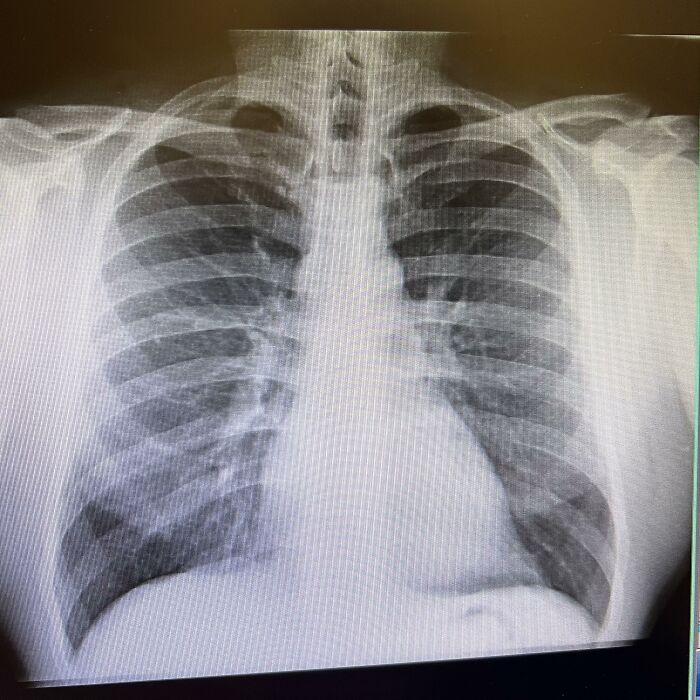

#11 Asymmetric Lungs

Check any diagram, and you’ll see lungs portrayed as a pair of identical twins, but they’re actually uneven, and for a good reason. The right lung has three lobes, while the left only has two, leaving room for the heart. This built-in asymmetry is strange because most organs are balanced, yet the chest is carefully crowded.

Anatomists noticed this a long time ago while mapping organ placement. Per Sci Rep, it aids airflow in the chest and improves filtration, removing most irritants before they reach the lungs and their extensive network of blood vessels and veins.

Evolution likely shaved a lobe off the left lung to solve the problem of fitting vital organs into a tight space. The asymmetry slightly reduces total air capacity, but it doesn’t usually cause breathing problems. Ultimately, lungs are proof that imperfections can provide surprising biological solutions.